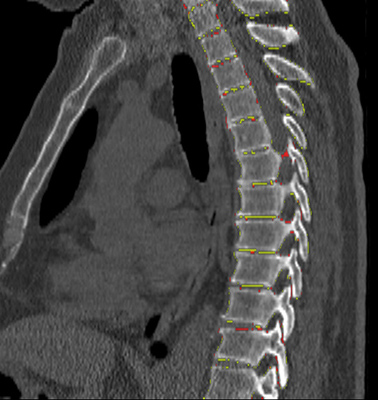

We trained and evaluated the method with five sets of CT and MR scans that visualize the spine. Reference segmentation masks for four of these datasets are publicly available, which allowed for a comparison with other publications that used the same data. Examples of images from the datasets are shown in Figure 3.

The thoracolumbar spine CT dataset consists of 15 dedicated spine CT scans that visualize all thoracic and lumbar vertebrae. It was originally used for the spine segmentation challenge held in conjunction with the Computational Spine Imaging (CSI) workshop at MICCAI 2014 (Yao et al., 2016). All subjects were young adults ( years) without vertebral fractures who were scanned with IV-contrast administration. The scans were reconstructed to in-plane resolutions of and slice thicknesses of . Semi-automatically obtained reference segmentations were provided by the challenge organizers. To allow for a comparison with the challenge results, we used the same data split with 5 scans for evaluation and the remaining 10 scans for training and development.

The xVertSeg.v1 dataset consists of 15 lumbar spine CT scans of subjects with compression fractures of various grades and types (Ibragimov et al., 2017). Manual reference segmentations are available for the lumbar vertebrae and were defined through a consensus reading of two observers. The scans were reconstructed to in-plane resolutions of and slice thicknesses of . There are currently two other publications that used the same dataset, but with different evaluation/training separation (Janssens et al., 2018; Sekuboyina et al., 2017). We therefore used the scans for evaluation and the remaining 10 scans for training.

The low-dose chest CT dataset consists of 55 scans from the National Lung Screening Trial (The National Lung Screening Trial Research Team, 2011). These scans were acquired for lung imaging and visualize in addition to the lungs a variable section of the thoracic and upper lumbar vertebrae. The scanned subjects were heavy smokers aged 50 to 74 years and therefore at increased risk for vertebral compression fractures due to their advanced age and smoking history. The scans were acquired with low radiation dose and reconstructed to in-plane resolutions of and slice thicknesses of . We created manual and semi-automatic reference segmentations for this dataset: 10 scans were used for evaluation and were therefore fully manually annotated by drawing along the contour of each vertebra in sagittal slices using an interactive live wire tool (Barrett and Mortensen, 1997). The contours were converted into segmentation masks, in which inaccuracies and other mistakes were corrected voxel-by-voxel. An additional set of 5 scans was annotated in the same way and was used to train a preliminary version of the network. This network was used to predict rough segmentations in the remaining 40 scans. These rough segmentations were manually inspected and corrected voxel-by-voxel, and were used for training of the final network. This strategy enabled us to create a large training set with substantially less manual annotation effort compared to fully manual segmentation, which is not necessarily needed for training data. Additionally, a second observer fully manually annotated two scans from the evaluation set for an estimation of the interobserver agreement. All fully manual and semi-automatic segmentations were performed in sagittal views by observers who received detailed instructions beforehand. Additionally, all segmentations were validated by an experienced radiologist.

The lumbar spine CT dataset consists of 10 scans of healthy subjects and corresponding manual reference segmentations of the lumbar vertebrae (Ibragimov et al., 2014; Korez et al., 2015). The scans were reconstructed to in-plane resolutions of and slice thicknesses of . Because this dataset is the smallest of the datasets that we included, it was used for an external evaluation of our supervised approach. Scans from this dataset were therefore only used for evaluation and were not part of the training set.

The lumbar spine MR dataset consists of 23 T2-weighted turbo spine echo MR images acquired at 1.5T in sagittal orientation (Chu et al., 2015). The scans have a resolution of . Manual reference segmentations are available for 7 vertebrae (T11-L5) in all scans. These reference segmentations contain only the vertebral bodies, not the entire vertebrae.